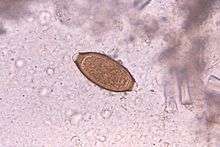

Adult worms are usually 3–5 centimetres (1.2–2.0 in) long, with females being larger than males as is typical of nematodes. The thin, clear majority of the body (the anterior, whip-like end) is the esophagus, and it is the end that the worm threads into the mucosa of the colon. The widened, pinkish gray region of the body is the posterior, and it is the end that contains the parasite’s intestines and reproductive organs. T. trichiura eggs are prolate spheroids, the shape of the balls used in Rugby and Gridiron football. They are about 50–54 µm (0.0020–0.0021 in) long and have polar plugs (also known as refractile prominences) at each end.

A stool ova and parasites exam reveals the presence of typical whipworm eggs. Typically, the Kato-Katz thick-smear technique is used for identification of the Trichuris trichiura eggs in the stool sample.

Trichuriasis can be diagnosed when T. trichiura eggs are detected in stool examination. Eggs will appear barrel-shaped and unembryonated, having bipolar plugs and a smooth shell.[16] Rectal prolapse can be diagnosed easily using defecating proctogram and is one of many methods for imaging the parasitic infection. Sigmoidoscopy show characteristic white bodies of adult hanging from inflamed mucosa (coconut cake rectum).